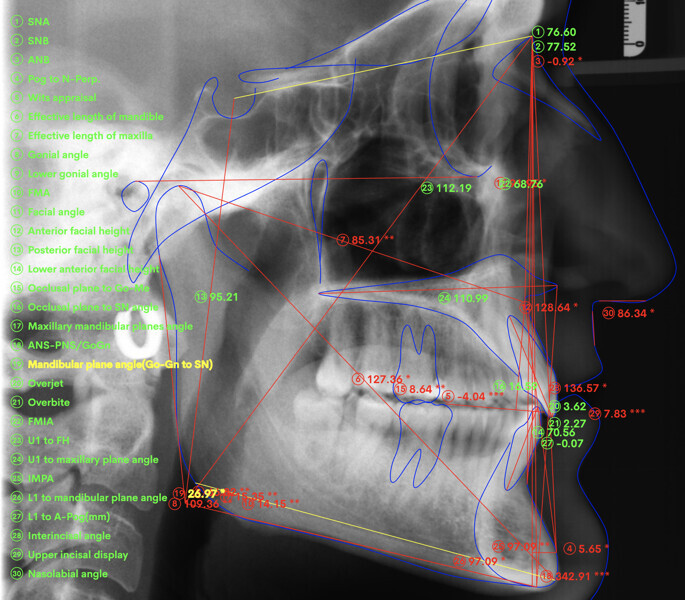

At the end of the treatment, Class I canine and molar relationships were obtained, maxillary incisor inclination was slightly increased (Ui–FH = 112°), mandibular incisor inclination (IMPA = 97.09°) was fully corrected by means of proclination and the divergency was slightly increased (SN–GoGn = 27°) because of the relative posterior extrusion and use of Class II elastics—a small variation (1°), which is interesting considering the age of the patient (Figs. 25–35). A balanced smile arc was obtained with an ideal relationship between the maxillary incisors and lower lip, and torque control of the lateral and posterior segments generated a broader smile.

The superimposition of the cephalometric tracings showed some interesting changes induced by the orthodontic treatment (Figs. 36 & 37):

The maxillary incisor inclination with respect to the maxillary plane was reduced by about 2° (from 110° to 112°), and the mandibular incisor inclination with respect to the mandibular plane was reduced by about 6° (from 91° to 97°). There was a good inter-incisal relationship and sufficient symphysis support.

The relative extrusion of the maxillary and mandibular molars, combined with the use of bite ramps, generated a slight clockwise rotation of the mandible (SN–GoGn from 26° to 27°), which allowed a further improvement of the overbite.

The proclination of the maxillary and mandibular incisors improved the profile and support of the lip.

When analysing the superimposed lateral cephalograms of both patients it is possible to detect the vertical pattern of the patients, how the deep bite was fully corrected, in both cases, using a combination of significant incisors proclination, and slight clockwise mandibular rotation induced by the relative posterior extrusion.